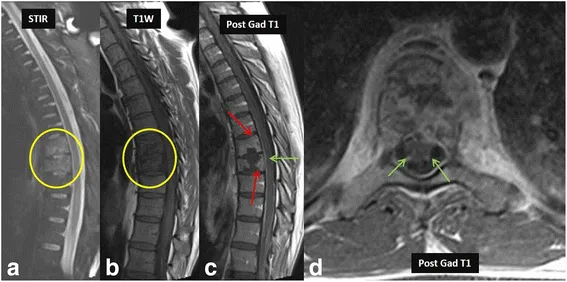

- Pyogenic Spondylodiscitis: S. aureus (MC). Hematogenous. Rapid disc destruction. MRI: T1↓, T2↑ disc/vertebrae, enhancement, abscess.

- Tuberculous Spondylitis (Pott's Spine): Thoracolumbar. Relative disc preservation (early). MRI: Subligamentous spread, large cold abscess, gibbus.

⭐ Pott's spine: Often multiple vertebral bodies, relative disc preservation (early), large cold abscess, subligamentous spread.

- Infection (TB/Pott's): Discitis, vertebral body destruction, paraspinal abscess.